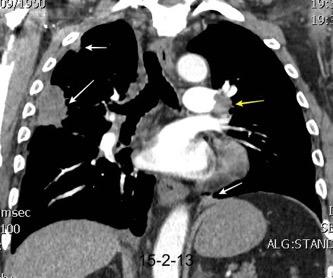

Marzo 2014: Perforación longitudinal distal secundaria a episodio de vómito (síndrome de Boerhaave). Derrame pleural izdo. que evoluciona a empiema.

Wang C-T et al. Tension hydropneumothorax in a Boerhaave syndrome patient: A case report . World J Emerg Med, 2021. Katabathina V et al. Nonvascular, nontraumatic mediastinal emergencies in adults:a comprehensive review of imaging findings. Radiographics. 2011.